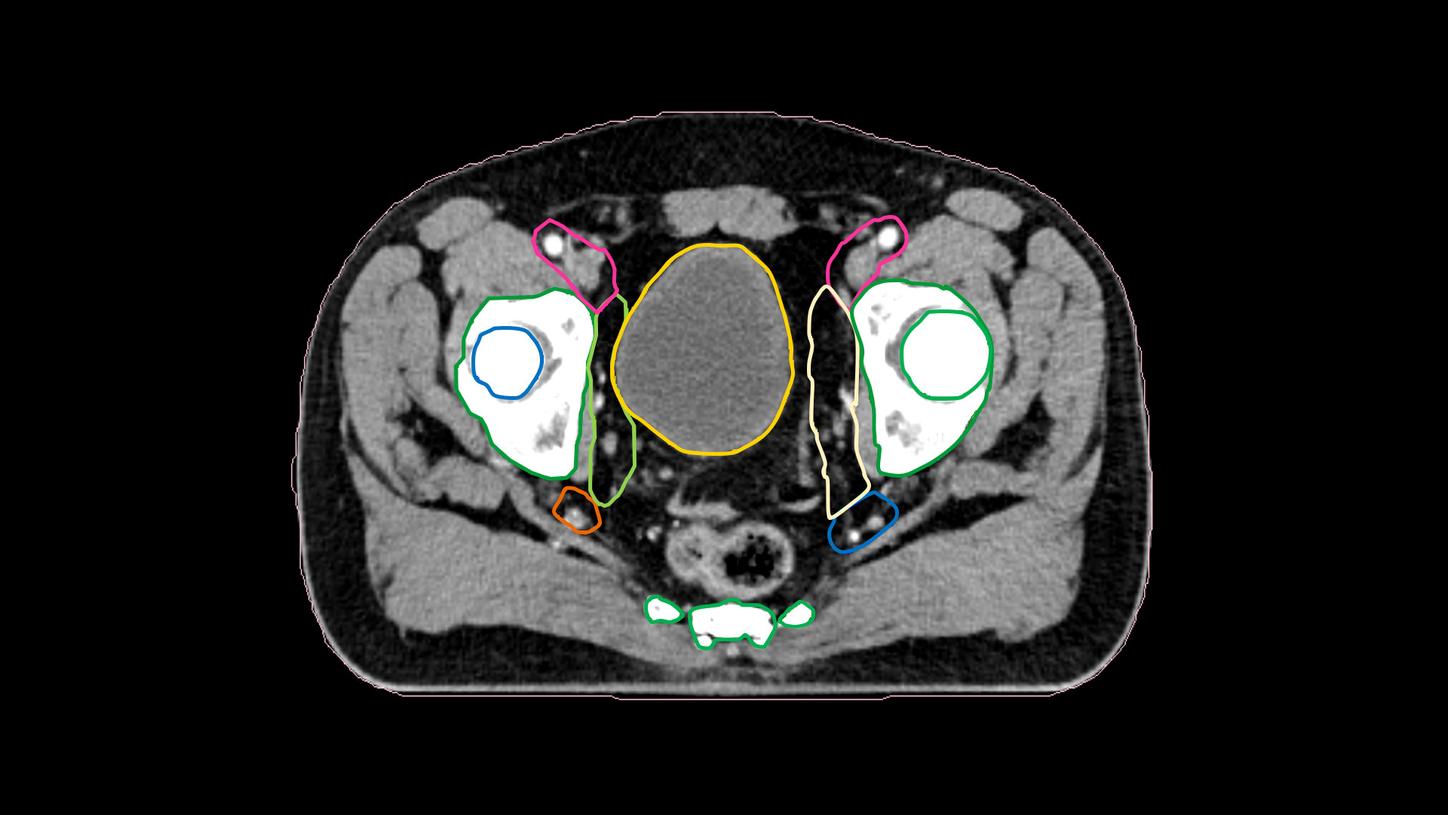

10) Intelligent Optimization Engine (IOE) works similarly to a human planner. The role of IOE is to replace manual, iterative planning, and produce clinically acceptable plans from initial planning to daily online adaptive plan generation.